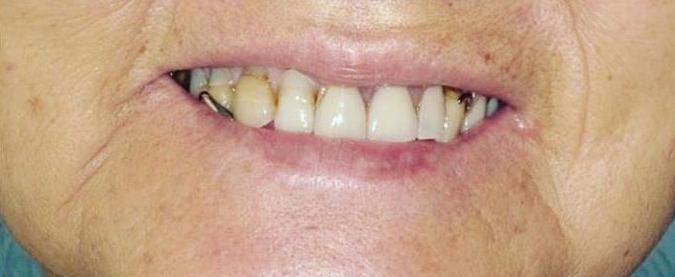

Can just four implants replace all of the teeth on the top or the bottom of your mouth? Thanks to advances in dental implant technology, that answer is a resounding yes.

Believe it or not, tooth loss is extremely common among adults, especially as we age. In fact, more than 35 million people in America are missing all of their upper and/or lower teeth. Rather than living with the discomfort and hassles of dentures, many people are opting for what is called “all-onfour” dental implant restoration.

All-On-Four: One Full Arch Of Teeth, Four Dental Implants

A Reason To Smile Again

able technique for replacing teeth, you should first understand what a dental implant is. An implant is a small titanium screw that fits inside your jawbone and replaces the root-part of a missing tooth. Minor surgery is required to insert the implants. Once the implant is in place, a crown is attached to give you a highly realistic-looking and functional prosthetic tooth.

Here’s where it gets really interesting: You do not need a dental implant for each and every one of your missing teeth. All you need is four precisely placed implants on the top of your mouth, and four on the bottom, to restore your full smile. That’s the beauty of the all-on-four. And because the implant is made of titanium, it has the unique ability to fuse to living bone and function as part of it. So eventually, the dental implant becomes part of the jawbone and serves as a strong, long-lasting foundation for your new teeth.

Besides ensuring that your implants are permanently fixed in place,

this bone fusion has another important benefit: it prevents future bone loss in the jaw. This helps to maintain a more youthful facial structure – and better oral health. But perhaps the biggest surprise about the all-on-four is how quickly it can transform your life.

All-On-4 Dental Implants: A Reason To Smile Again

To fully understand this remarkable technique for replacing teeth, you should first understand what a dental implant is. An implant is a small titanium screw that fits inside your jawbone and replaces the root-part of a missing tooth. Minor surgery is required to insert the implants. Once the implant is in place, a crown is attached to give you a highly realistic-looking and functional prosthetic tooth.

Besides ensuring that your implants are permanently fixed in place, this bone fusion has another important benefit: it prevents future bone loss in the jaw. This helps to maintain a more youthful facial structure – and better oral health. But perhaps the biggest surprise about the all-on-four is how quickly it can transform your life.